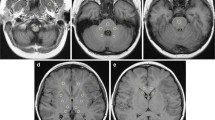

The mixed linear model analysis showed a significant effect of number of GBCA administrations both on globus pallidus:thalamus (F[8]=3.09; P=0.002) and on dentate nucleus:pons (F[8]=2.36; P=0.021) (Fig. 2).

A significant difference between the first and last administration in both the globus pallidus:thalamus (P=0.004) and the dentate nucleus:pons (P=0.001) was observed, demonstrating higher values in the last administration. Mean globus pallidus:thalamus values at the first and the last MR examinations were: 1.06±0.04 (SD) and 1.09±0.05. Mean dentate nucleus:pons values at the first and last MR examinations were: 0.95 ± 0.06 and 1.02±0.06. No significant differences in baseline MR globus pallidus:thalamus and dentate nucleus:pons between patients and controls were observed (respectively, P = 0.16 and P = 0.15) and mean signal intensity ratios in the control group were 1.07 ± 0.05 for the globus pallidus:thalamus and 0.96±0.05 for the dentate nucleus:pons (Fig. 3).